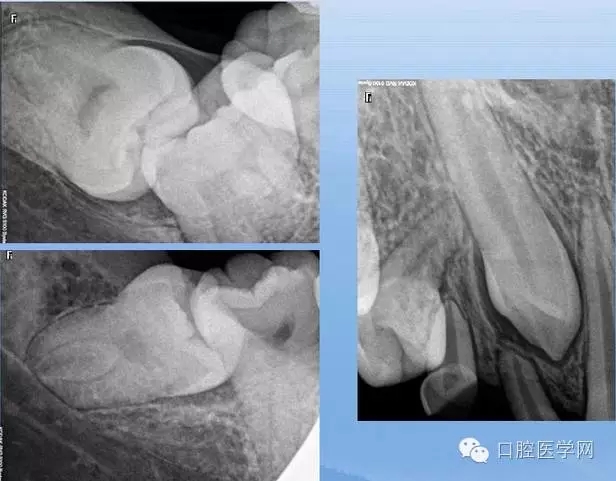

4.阻生牙

最常見于下頜第三磨牙

X線表現(xiàn):確定阻生牙的位置;確定阻生方向;牙根數(shù)目和形態(tài);阻生牙有無齲齒和根尖情況;與第二磨牙的關(guān)系;與下頜管的距離和磨牙后間隙的大小。